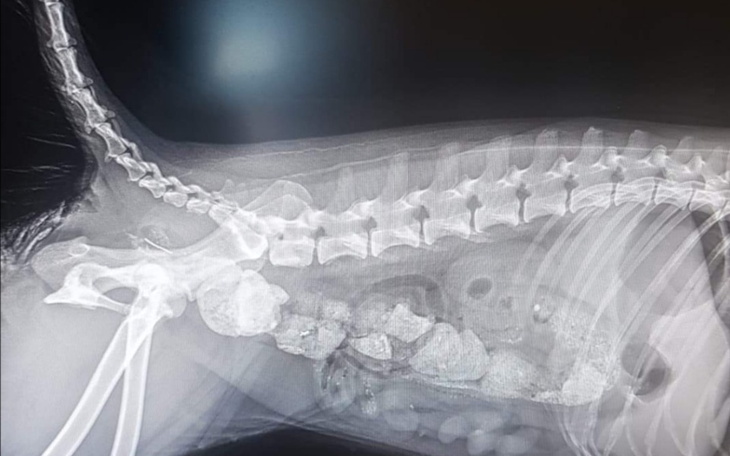

Może moje życie nie było złe, ale micha już nie ta, tata nie dbał już o mnie tak jak kiedyś, czasami dawał kości i to stało się moją kolejną tragedią...

Moje jelita się zatkały, nie mogłam się załatwić, ciągle bolał mnie brzuszek i przez to byłam smutna i każdego dnia coraz chudsza. Bałam się że zniknę tak jak mamusia 😢. Parszywy psi los. Mój tata nie dawał już rady i poprosił o pomoc Pani, która kiedyś mnie znalazła. Nie odmówiła i dzięki temu jeszcze żyję. Gdyby nie ona, dolaczyłabym pewnie do mamy, ale mimo, że bardzo za nią tęsknię CHCĘ ŻYĆ. Przeszłam ciężką operację i niestety nie mogę już wrócić do taty, bo wymagam póki co stałej opieki i specjalnego żywienia. Choć to boli, to rozumiem, że tak musiało być, abym nadal mogła cieszyć się życiem, biegać po zielonej trawie. Jest tylko jedna sprawa, która odbiera mi chęci i radość z tego, że już nic nie boli. To dług za moją operację i to, że teraz jedzonko, które muszę jeść jest bardzo drogie, a ja nie mam na to pieniążków 😢